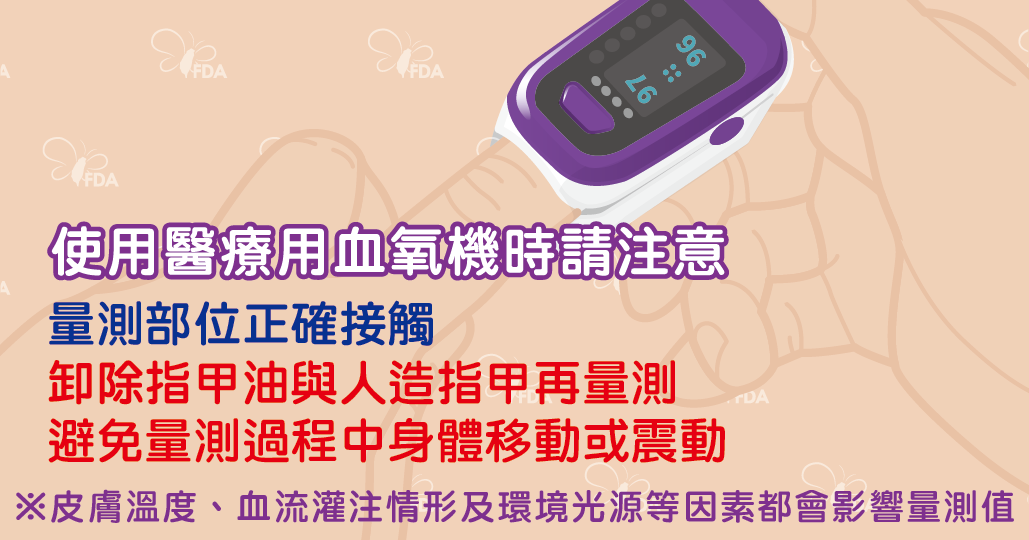

超夯血氧機,學會正確操作與判讀!

醫療用血氧機可用於測量及顯示動脈血氧飽和度(SpO2)及脈搏率(pulse rate)等資訊,是評估患者是否缺氧的利器,屬於第二等級醫療器材。其原理是以光學方式進行非侵入量測,利用含氧血紅素與去氧血紅素對不同波長的光吸收度差異,可計算出兩種血紅素光訊號的比例,進而推算出血氧飽和度。

什麼是血氧?血氧機該怎麼用?

新冠肺炎爆發後,不少民眾擔心COVID-19感染可能造成肺部發炎、降低血氧濃度,導致市售血氧機賣到缺貨!究竟什麼是血氧?使用時有哪些注意事項?食品藥物管理署(下稱食藥署)邀請家醫科黃農茵醫師為大家詳細說明。